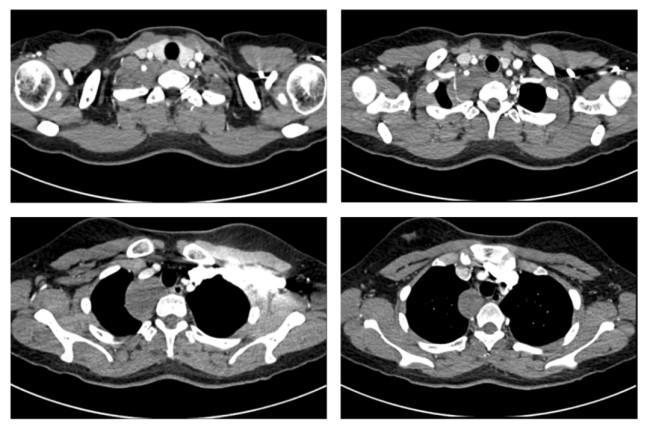

患者是一名来自新疆的19岁女生,在校期间一次常规体检中偶然发现后纵隔肿物。因肿物位置特殊,患者及家属在当地多家医院辗转求医,最终慕名到省立医院刘相燕主任处就诊。入院后,患者完善了胸部CT平扫+增强检查,影像显示,肿物上缘至甲状腺水平,向下沿气管及食管走行,累及长度近6厘米,与右锁骨下动脉关系密切,几乎完全包绕椎动脉。此外,肿瘤已累及交感神经,紧邻臂丛神经,术中稍有不慎极易损伤重要的血管、神经,导致严重的并发症。这极大增加了手术难度与风险,对手术团队提出了挑战。针对患者复杂的病情,刘相燕主任带领团队制定了详尽的手术方案,就手术切口选择、术中突发状况应急处理以及术后生命体征与神经功能监测等环节均进行了充分讨论与周密准备。

患者术前胸部增强CT影像资料